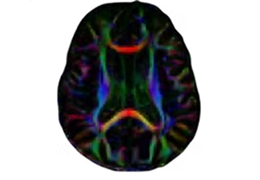

Eclipse 成像智能功能提供强大的处理能力和最佳质量的影像,同时减少质量错误并提高剂量效率。

凭借 AI、专有算法和先进的影像处理能力,提供出色的影像质量和无与伦比的诊断信心。